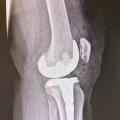

• les interventions prothétiques non conservatrices (fig. 1).

Insatisfaction du patient en postopératoire

Le médecin traitant peut être interrogé sur un résultat jugé insuffisant par le patient, après (ou non) avis du chirurgien. Cette situation n’est pas rare, notamment après prothèse articulaire : 2 % environ pour les prothèses de hanche et jusqu’à 20 % pour les prothèses de genou. Les plaintes sont variables et parfois associées (douleurs persistantes, mobilité incomplète, gênes fonctionnelles ou sportives). Le médecin peut se trouver alors en position délicate entre son patient et le chirurgien. Il est important de reprendre les échanges de courrier, notamment l’examen et l’information préopératoire. Les suites chirurgicales peuvent également expliquer ces diffi­cultés. Le résultat fonctionnel complet s’obtient généralement après six mois pour une pose de prothèse de hanche et un an après la pose d’une prothèse de genou, et certains dysfonctionnements sont de diagnostic difficile. Le plus souvent, des explications répétées suffisent. ­Toutefois, dans certains cas, un second avis chirurgical peut être pertinent. En revanche, il convient d’éviter la pres­cription de bilans d’imagerie, parfois inappropriés, comme une scintigraphie précoce moins d’un an après la pose de prothèse. En effet, des images ambiguës et non spécifiques peuvent orienter vers un diag­nostic erroné et favoriser l’évolution vers un conflit médico-légal.